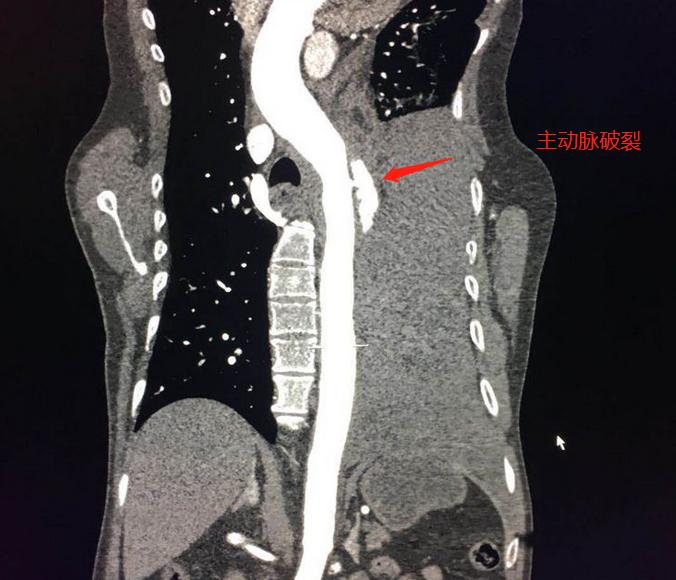

医院胸痛中心一键启动,绿色通道做急诊胸部CT:

左侧大量胸腔积液,并且有分层现象,提示有为胸腔出血,考虑主动脉破裂,建议紧急CTA(主动脉造影检查)明确病变部位和范围。

胸外科主任在旁边监测生命体征,放射科主任亲自扫描,30分钟内完成造影扫描、后处理、出具影像报告(第2道):

主动脉弓部见不规则瘤样扩张影,以窄径与主动脉相连,符合壁间血肿并假性动脉瘤、穿透性溃疡。需要马上手术修补封堵。